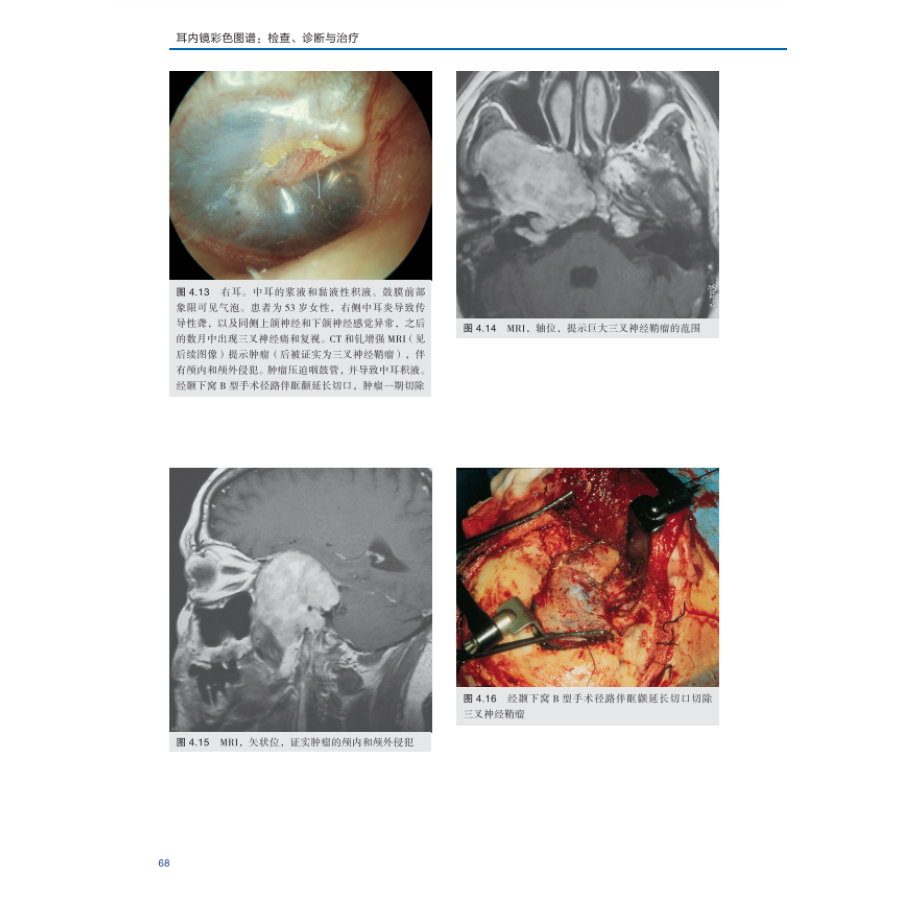

4.2 继发于肿瘤的分泌性中耳炎